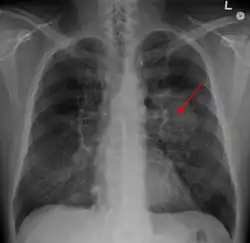

A previously healthy 16-year-old male presented with progressive shortness of breath, cough, and hypoxemia in the setting of several months of daily nicotine and THC-containing e-cigarette use. He had been suffering from a chronic cough and intermittent nausea since he started vaping several months before presentation. His cough worsened 1 week before admission to the hospital, accompanied by vomiting induced by coughing and non-bloody diarrhea. He subsequently developed a fever and was evaluated in an Emergency Department. A chest radiograph showed a right lower lobe pneumonia prompting outpatient treatment with bacterial infection medication (Shah et al., 2020). |